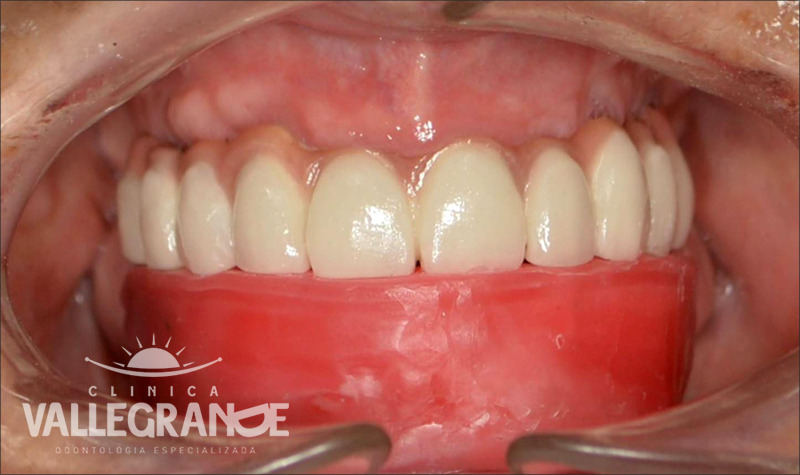

Rehabilitación oral total con prótesis inferior sobre implantes y coronas superiores.

Prótesis híbrida inferior de cerámica fija sobre implantes.